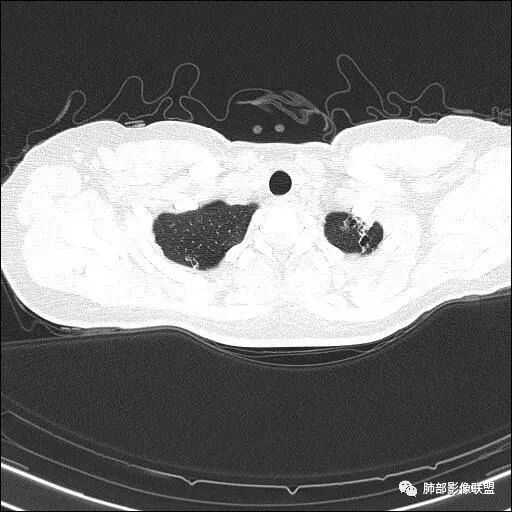

【每日晨读】双肺上叶多发薄壁空洞

两肺多发病灶

分布特点:上肺胸膜下

2.双肺多发薄壁空洞影、条索影及结节影,边界较清楚,密度偏高不柔和,散乱,但有成簇倾向或堆积感,胸膜下分布为主,双肺上叶分布为主。

3.空洞相当不规则,缺乏张力,未见血管穿行,未见壁结节,未见液平。

4.双肺门及纵隔未见肿大淋巴结。未见胸腔积液。